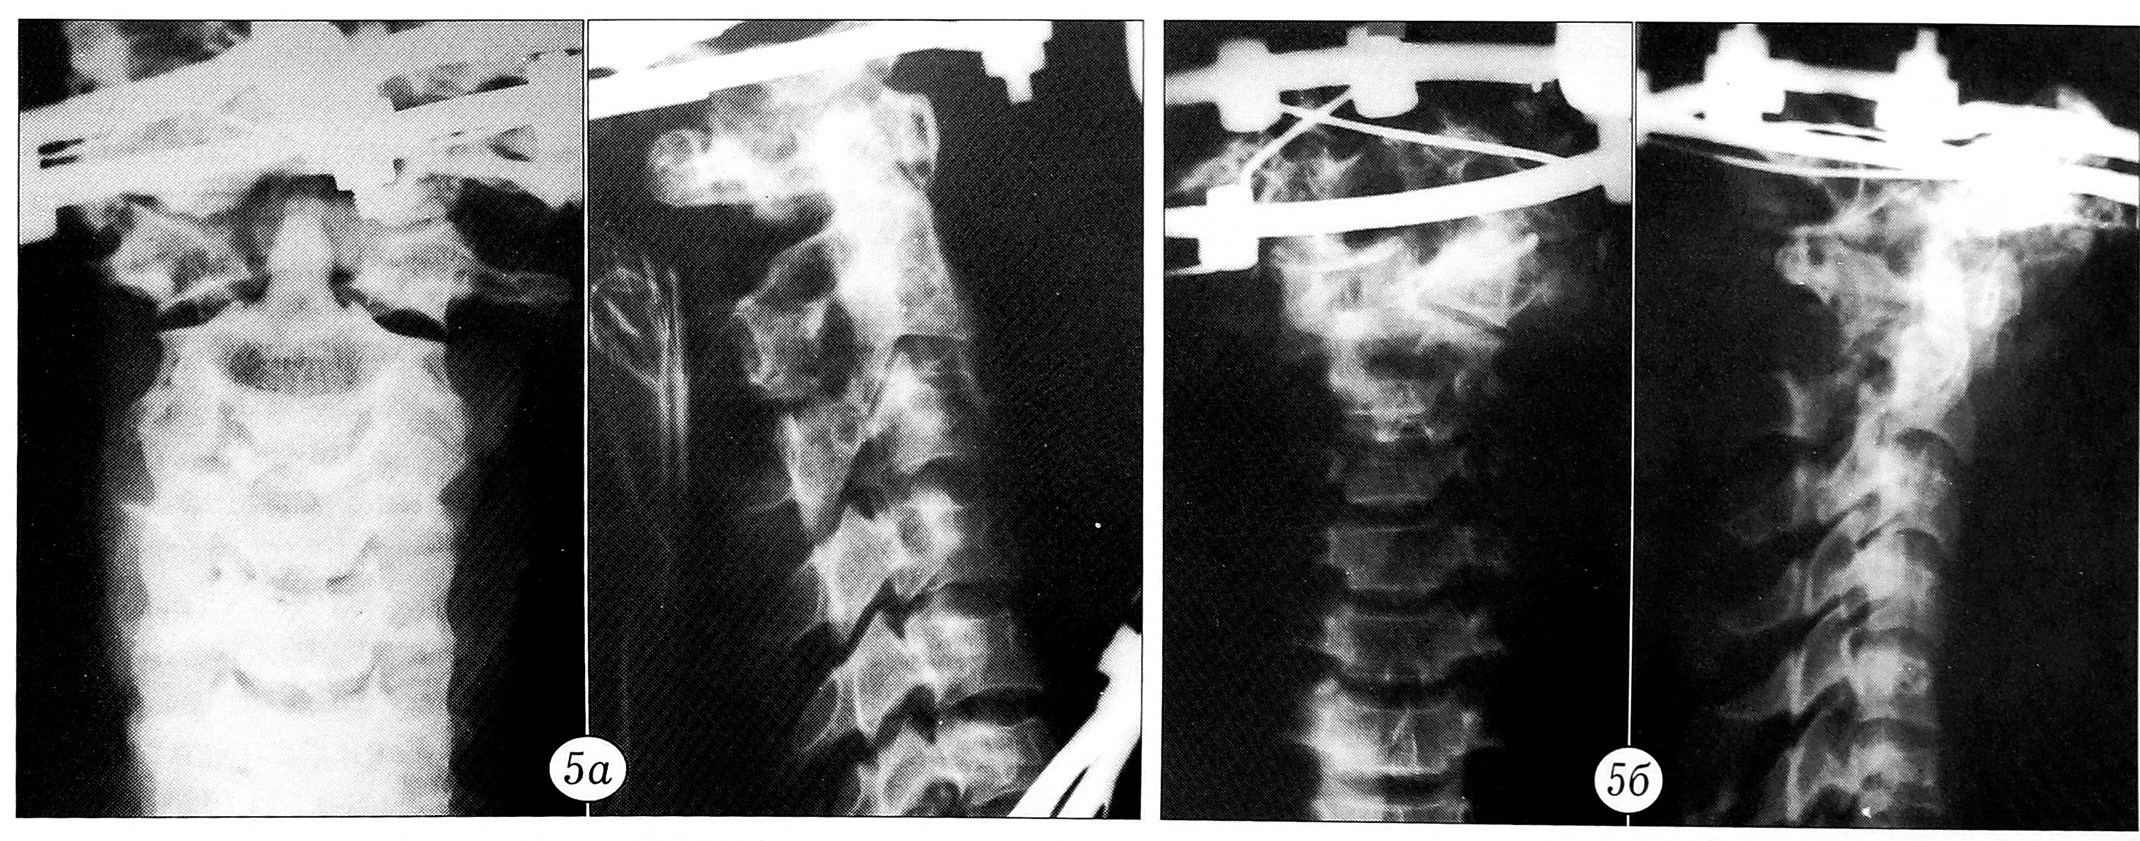

Результаты нагрузочного теста документировались графически. По оси ординат регистрировалось усилие в ньютонах, по оси абцисс — степень смещения позвонков в миллиметрах (рис. 2). При этом основное внимание уделялось величине нагрузки, при которой происходило наибольшее смещение позвонков. До и после нагрузочного теста производилась рентгенография блоков (рис. 3~5).

Рис. 4. Перелом «палача» типичный до (а) и после (б) нагрузочного теста.